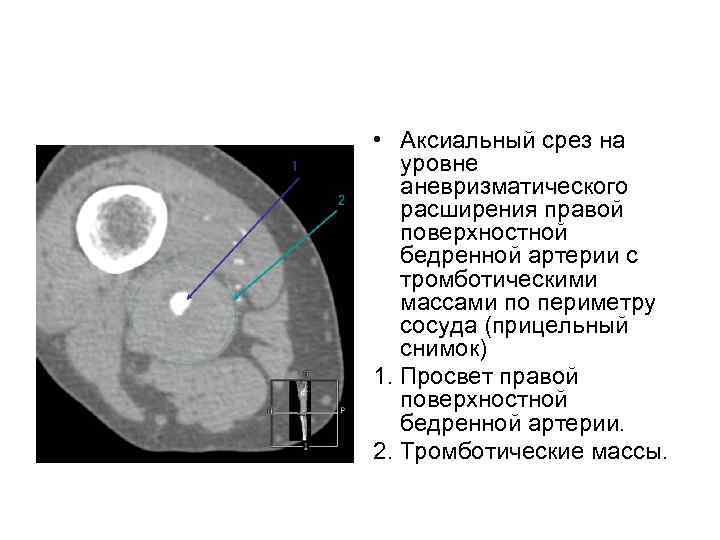

• Аксиальный срез на уровне аневризматического расширения правой поверхностной бедренной артерии с тромботическими массами по периметру сосуда (прицельный снимок) 1. Просвет правой поверхностной бедренной артерии. 2. Тромботические массы.